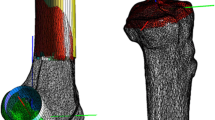

These measurements were taken in the CHK first, fixing the clusters by Steinmann pins. The clusters were then moved to the ADK and fixed by minimally invasive unicortical Schanz screws. The manual laxity tests were repeated and collected by the system before surgery, after isolated IAR and finally after the additional minimally invasive ALR. For IAR, the autologous semitendinosus tendon was taken and prepared for a short four-bundle single-tunnel montage, whose extremity graft was fixed 15 mm inside the tibial bone tunnel. The femoral tunnel was drilled by the anteromedial portal, and femoral fixation was secured with a transverse cross-pin system inserted close to the femoral entry tunnel (Fig. 1a). The graft was pre-tensioned for 10 min at 10 Newton and subsequently fixed at 30° of knee flexion with manual tensioning enabling the knee to be lifted from the operating table. The ALR [24] involved folding the autologous gracilis tendon and making a free 11-cm-long graft, inserted from a femoral position 1 cm proximal and posterior to the lateral epicondyle to a tibial margin position against the posterior aspect of the Gerdy’s tubercle. Interference screws inside bone tunnels were used for femoral and tibial fixation of the graft. Drilling the tunnels, inserting the graft and fixing it with interference screws were performed through two 1.5-cm-long incisions. Between them, graft application was completed by blunt dissection under the fascia lata through the distal incision with crocodile forceps (Fig. 1b). The graft was secured with 90° of knee flexion and 0° of internal–external rotation.